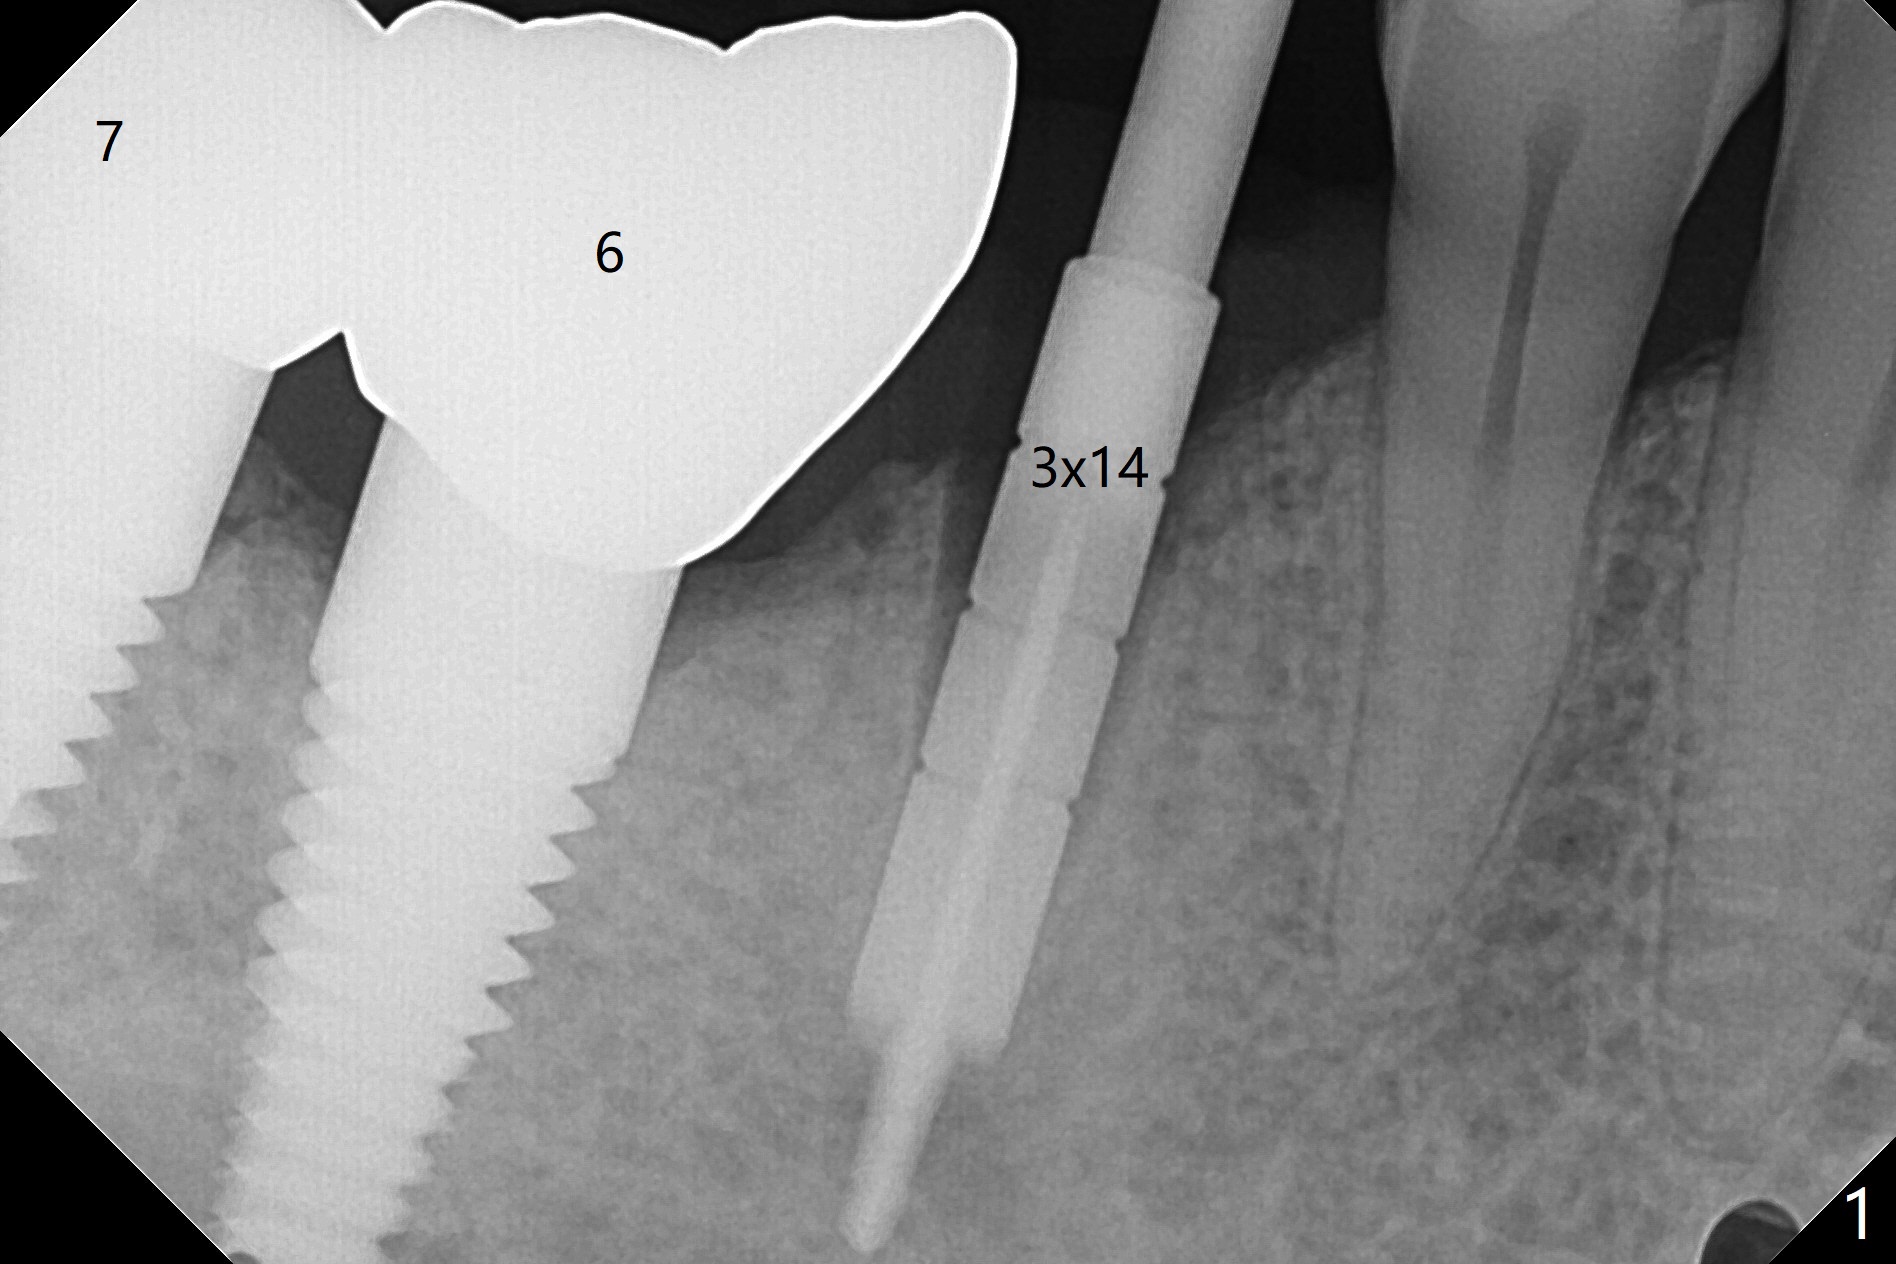

徒手即刻种植缺点是钻洞深度控制不易,尤其是术前设计是骨水平植体,而术中决定使用软组织水平植体。当3毫米reamer达到14毫米深度(骨水平)时,略感到根尖骨质长度。可欣的是4乘17毫米软组织水平植体取得初步稳定性(图二),即刻放置基台(3.5乘5毫米)后,骨粉放入颊侧间隙,有意地把骨粉推向远中(图二:*),好像植体接近颏神经(图二:红色),不过术后没有神经麻木现象,术后分析术前CT表明植体离神经相当远(图三)。术后四个月病人回来做修复,这时我们不关心深部神经了,重点是牙槽嵴周围骨质与植体愈合如何。可以使用sensor 1 (一号传感器,图四:1)和根尖片固定器(黄色,这样减少病人疼痛,恶心,容易放置,拍摄影像好,平行)或者sensor 2(图四:2)加咬翼片固定器(红色,同样容易放置,拍摄影像好,平行,植体螺纹清晰);为了拍摄下颌牙齿多些,传感器放低些(相对于固定器,图四,五),结果得到的信息足够(图六),好像植体已经整合,接着取模。There is no residual cement immediately post cementation with a small escape hole occlusally (Fig.7).